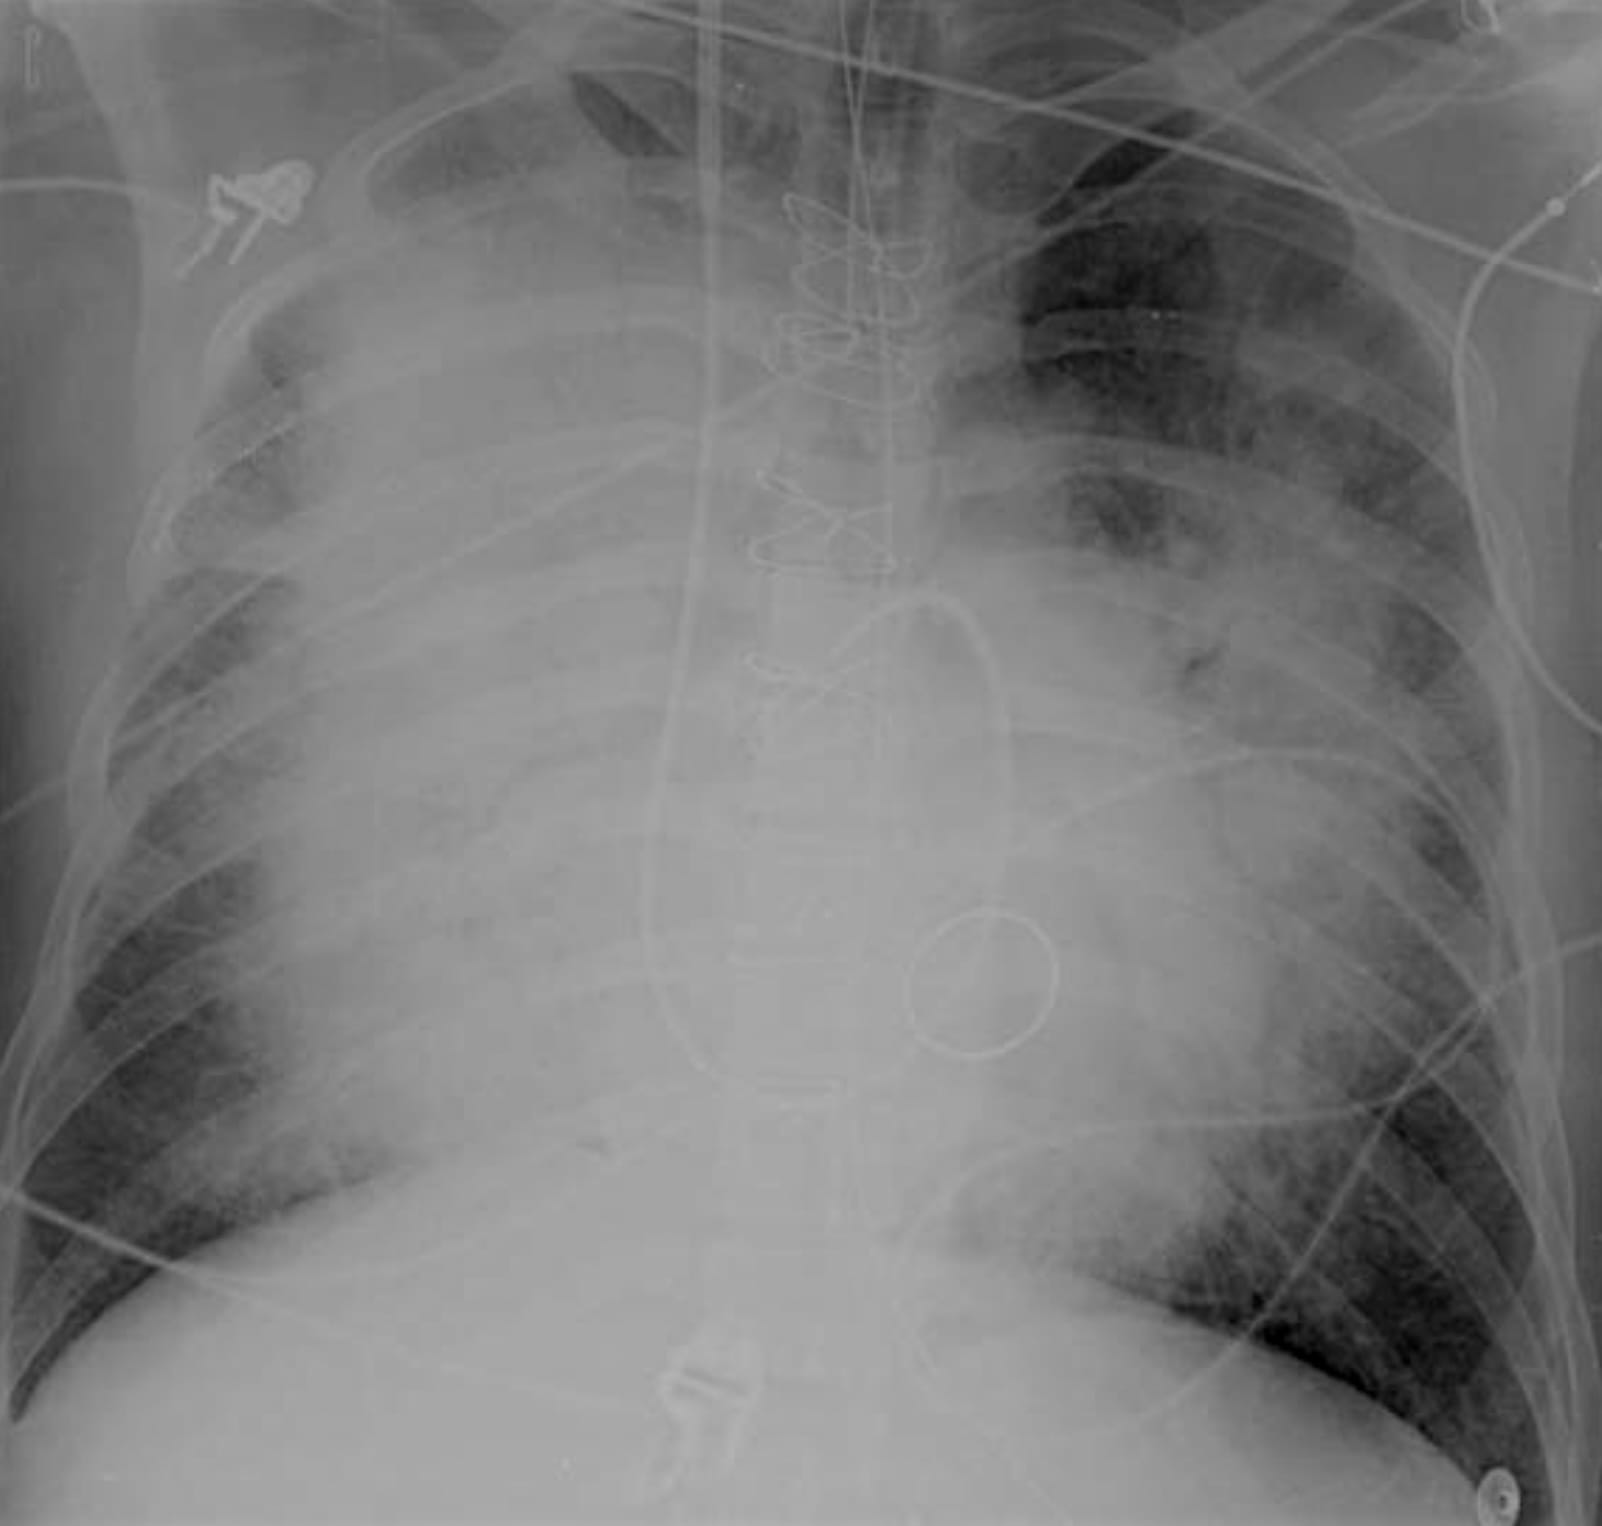

The distribution of edema fluid (consolidation) is typically diffuse and symmetric.

CT of Acute Lung Injury Edema

Don’t confuse the posterior lung opacities with anything else other than consolidated and —particularly—atelectatic lung. This is potentially so-called recruitable (by different ventilatory strategies) lung.